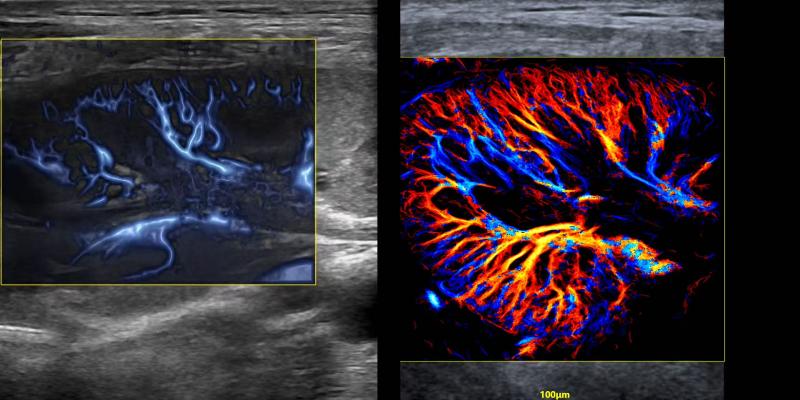

2024年、飛依諾はURM超高解像度の顕微畫像技術を開発したことを発表した。この技術は臨床と科學研究活動にかつてない真新しい超音波の視野を切り開き、業界の専門家から「今後10年間に超音波業界で最も重要な技術的突破」と評価された。

現在、全國で100以上の三甲病院がこの製品を使用して臨床研究を行っている。さらに、ヨーロッパ、南米、アジアなど世界各地からのトップクラスの専門家は飛依諾と協力して関連する科學研究も行っている。